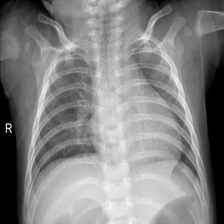

图像分类是计算机视觉的重要领域,它的目标是将图像分类到预定义的标签。许多研究者提出了很多不同种类的神经网络,并极大地提升了分类算法的性能。本次实践将训练ResNet模型实现对胸部CT影像的分类,以区分新冠肺炎患者、病毒性肺炎患者以及正常人。

新冠肺炎在全球爆发以后,来自卡塔尔、孟加拉国、巴基斯坦以及马来西亚的研究人员与医生合作,建立了一个包含正常人、病毒性肺炎患者、新冠肺炎患者的胸部CT影像的数据集。数据集包含1200个新冠阳性患者的影像、1341个正常人的影像和1345个病毒性肺炎患者的影像。

图1的真实标签:正常肺部,预测结果:正常肺部

图2的真实标签:病毒性肺炎,预测结果:病毒性肺炎

图3的真实标签:新冠肺炎,预测结果:新冠肺炎